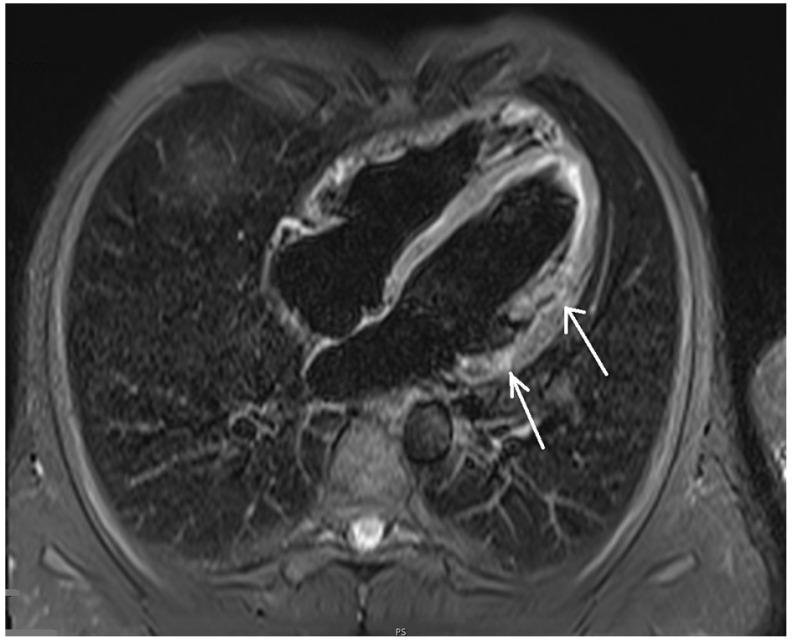

This article presents the case of a 29-year-old male patient, addicted to prescribed medical marijuana administered for mixed anxiety and depressive disorder and without classic cardiovascular risk factors and history of myocarditis, suffering from episodes of paroxysmal hemodynamically unstable ventricular tachycardia. Cardiovascular magnetic resonance imaging of the heart revealed disseminated non-ischemic myocardial injury lesions of subepicardial and intramuscular location. Additionally, the individual experienced myocardial infarction without ST segment elevation following marijuana intake. Treatment required implantation of a cardioverter-defibrillator and ablation of the myocardial areas responsible for the origin of the arrhythmia, as well as appropriate pharmacotherapy and marijuana addiction treatment.

本文介绍了一名29岁男性患者的病例,该患者因混合性焦虑和抑郁障碍而服用处方医用大麻成瘾,无典型心血管危险因素及心肌炎病史,却出现阵发性血流动力学不稳定的室性心动过速发作。心脏心血管磁共振成像显示,心外膜下和肌内有散在的非缺血性心肌损伤病灶。此外,该患者在吸食大麻后发生了无ST段抬高的心肌梗死。治疗需要植入心脏复律除颤器,消融导致心律失常起源的心肌区域,并进行适当的药物治疗和大麻成瘾治疗。